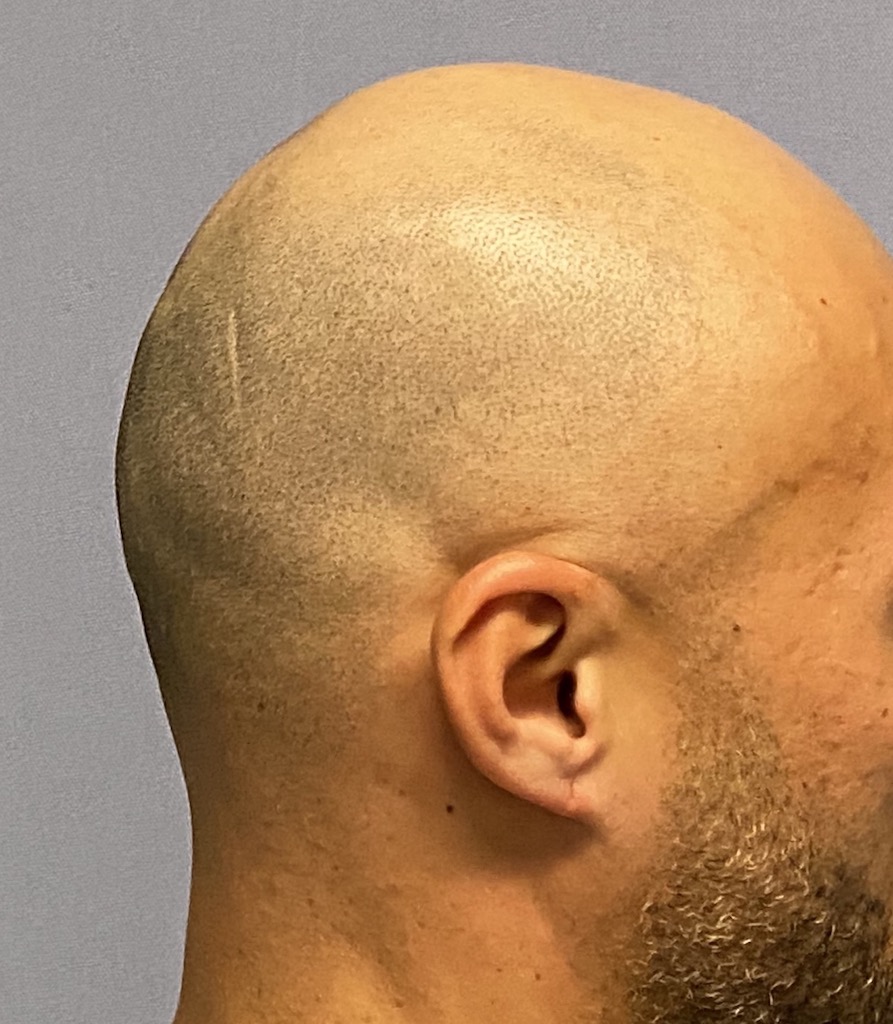

Desire for reshaping of an asymmetric flat back of the head in a shaved head male.

A combined back of the head reshaping procedure was done with a custom skull implant, sagittal ridge reduction and a right temporal muscle reduction.

Desire for reshaping of an asymmetric flat back of the head in a shaved head male.

A combined back of the head reshaping procedure was done with a custom skull implant, sagittal ridge reduction and a right temporal muscle reduction.